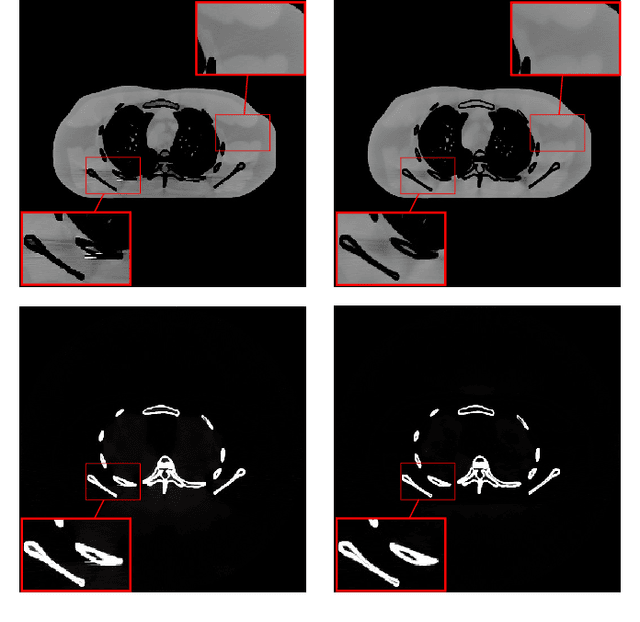

Dual energy computed tomography (DECT) imaging plays an important role in advanced imaging applications due to its material decomposition capability. Image-domain decomposition operates directly on CT images using linear matrix inversion, but the decomposed material images can be severely degraded by noise and artifacts. This paper proposes a new method dubbed DECT-MULTRA for image-domain DECT material decomposition that combines conventional penalized weighted-least squares (PWLS) estimation with regularization based on a mixed union of learned transforms (MULTRA) model. Our proposed approach pre-learns a union of common-material sparsifying transforms from patches extracted from all the basis materials, and a union of cross-material sparsifying transforms from multi-material patches. The common-material transforms capture the common properties among different material images, while the cross-material transforms capture the cross-dependencies. The proposed PWLS formulation is optimized efficiently by alternating between an image update step and a sparse coding and clustering step, with both of these steps having closed-form solutions. The effectiveness of our method is validated with both XCAT phantom and clinical head data. The results demonstrate that our proposed method provides superior material image quality and decomposition accuracy compared to other competing methods.